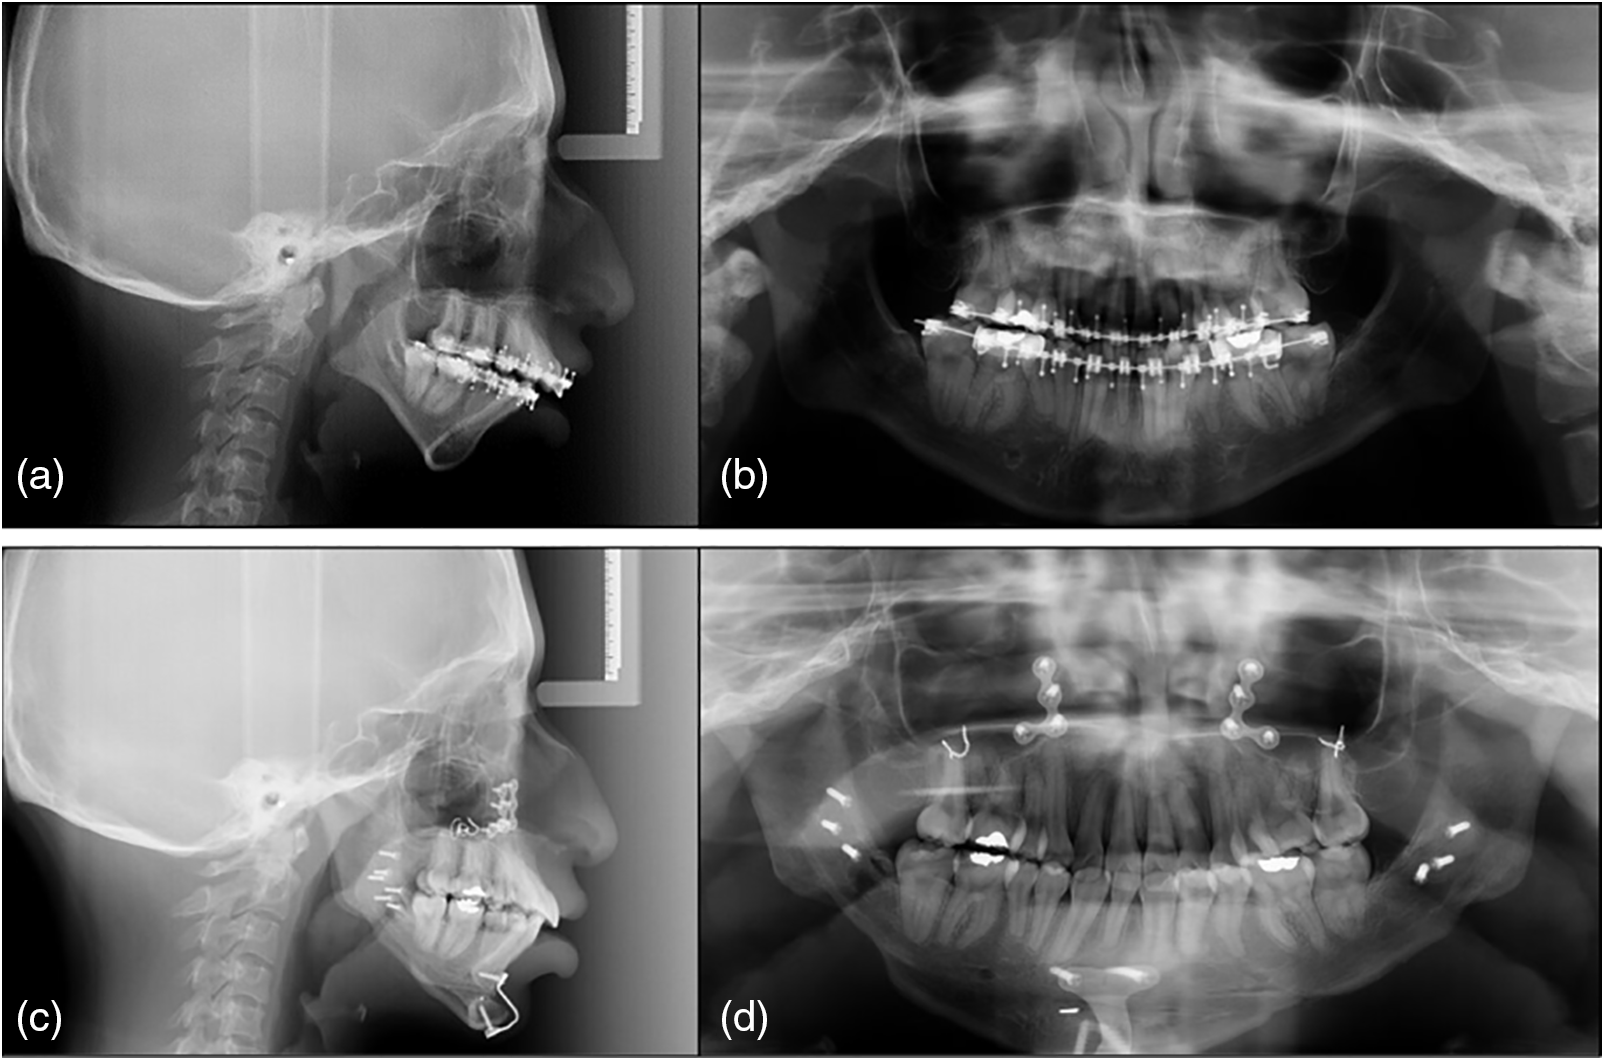

After orthodontic decompensation, adequate correlation was achieved with an overjet of 11 mm and an overbite of 3 mm, and then orthognathic surgery was performed, under balanced general anesthesia with fibroscope-guided intubation to avoid airway complications and reduce the morbidity associated with this syndrome. The following surgical procedures were performed:

Le Fort I osteotomy: A 5 mm mandibular intrusion was performed with a mandibular response. Surgical planning was performed considering a previous cephalometric prediction and performing the procedure (Figs. 2a, 2b).

Fig. 2. Presurgical photographs: a) Frontal extraoral at rest, b) Frontal extraoral smile, c) right lateral extraoral, d) right overbite, e) frontal overbite, f) left overbite, g) intraoral superior occlusal, and h) intraoral lower occlusal.

Postoperative: For one week after surgery, the patient wore a splint, as well as class II elastics (from the upper canine to the first lower molar) with a resistance of 6 1/4 oz. A follow-up radiograph was obtained one week after surgery, including lateral, panoramic, and postero-anterior cephalometry (Fig. 4).

Fig. 5. Lateral radiograph of the skull: a) Preoperative, b) Postoperative. Panoramic radiograph c) preoperative, and d) postoperative.